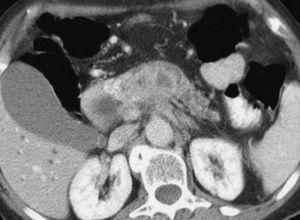

A partir de la complementación de la US con técnica de doppler color ha mejorado el rendimiento de la misma en la evaluación de la extensión tumoral a los vasos arteriales y venosos peripancreáticos, que oscila entre el 84 y el 87%3,4 (fig. 1). Tomiyama et al5 evaluaron la extensión vascular arterial tumoral en 33 pacientes mediante US doppler color, comparando sus hallazgos con los de la angiografía, la cirugía y la pieza de resección. En los 11 pacientes intervenidos describen una sensibilidad del 60%, especificidad del 93% y rendimiento diagnóstico del 87%. En la evaluación conjunta de todos los pacientes incluidos en el estudio concluyen que la US doppler color ofrece un rendimiento diagnóstico superior al de la tomografía computarizada (TC) (72%) y similar al de la angiografía (91%). No obstante, el escaso número de pacientes con correlación patológica supone, en cierto modo, una limitación a las conclusiones de los autores. Hasta donde hemos podido revisar Minnitti et al6 presentan los mejores resultados publicados por el momento, detectando el adenocarcinoma pancreático mediante US en 61 de los 64 pacientes incluidos en su estudio (95,3%), y obteniendo mejores resultados que la TC helicoidal, cuyo índice de identificación tumoral fue del 89,1%. El tamaño promedio de los tumores detectados en la US fue de 3,2 cm (rango: 1,5-6,8 cm), aunque los autores no presentan la correlación patológica del tamaño tumoral medido en la pieza quirúrgica en los 18 casos en los que se pudo llevar a cabo la resección radical del tumor. Los autores presentan un índice de predicción de resecabilidad del 81,4% para la US, algo inferior al obtenido por la TC (86,0%), calculado sobre los 43 pacientes laparotomizados de la serie. Sin embargo, estos buenos resultados no han sido refrendados en la literatura por otros autores hasta el momento.

Fig. 1.--Ecografía abdominal. (A) masa hipoecoica de 8 4, 5 cm en la cola del páncreas, en íntimo contacto con la vena esplénica (2). (B) Estudio doppler color y pulsado que demuestra la permeabilidad de la vena esplénica con un registro sin alteraciones.